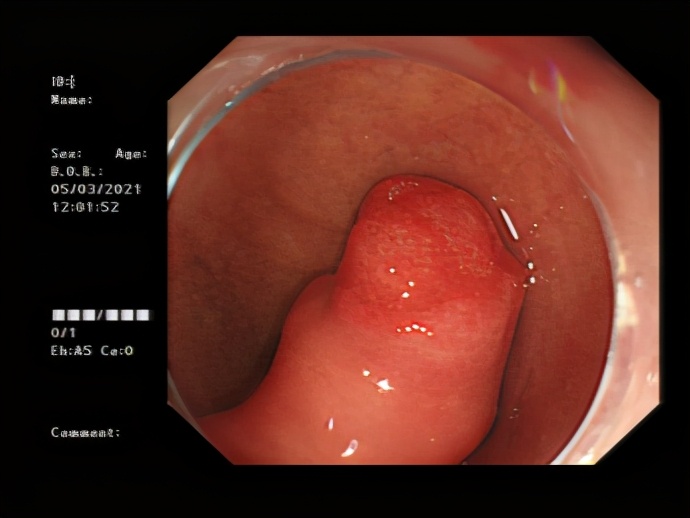

做胃镜检查时,在许女士的十二指肠发现一个大肿物, 形状类似手指,占据了十二指肠球部1/2空间。如果肿物持续存在,可能出现出血、梗阻等风险,必须手术切除。

在南方医科大学南方医院帮扶专家、我院副院长兼消化内科学科带头人李跃副主任医师带领下,消化内科诊疗团队高效率运转,完成术前检查及术前评估,在许女士入院第二天完善超声内镜检查,并在 内镜下行肿物切除术, 大小约4.0x2.5cm,术中出血0ml。

△ 内镜下表现